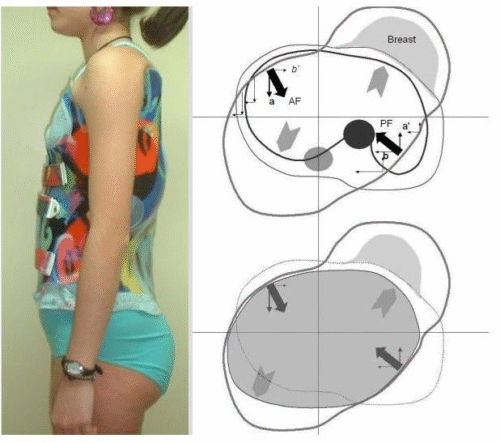

1) اختيار نوع حزام غير مناسب لنوع الانحناء

بعض الانحناءات تحتاج حزام 3D

اختيار النوع الخاطئ = نتيجة ضعيفة.

3) عدم ضبط نقاط الدفع (Pressure pads)

إذا لم تكن نقاط الدفع موضوعة بدقة على قمة الانحناء، فلن يحدث أي تصحيح.

تغيير الحزام لنوع 3D إذا كان النوع القديم غير مناسب

التطور الكبير في تصميم الأحزمة الطبية جعل علاج اعوجاج العمود الفقري عند المراهقين أكثر نجاحًا وأقل إزعاجًا. باستخدام تقنيات التصوير الثلاثي الأبعاد والمحاكاة الرقمية، أصبح الحزام أكثر خفة وراحة، ويعطي نتائج أفضل في تصحيح الانحناء والتواء العمود الفقري.